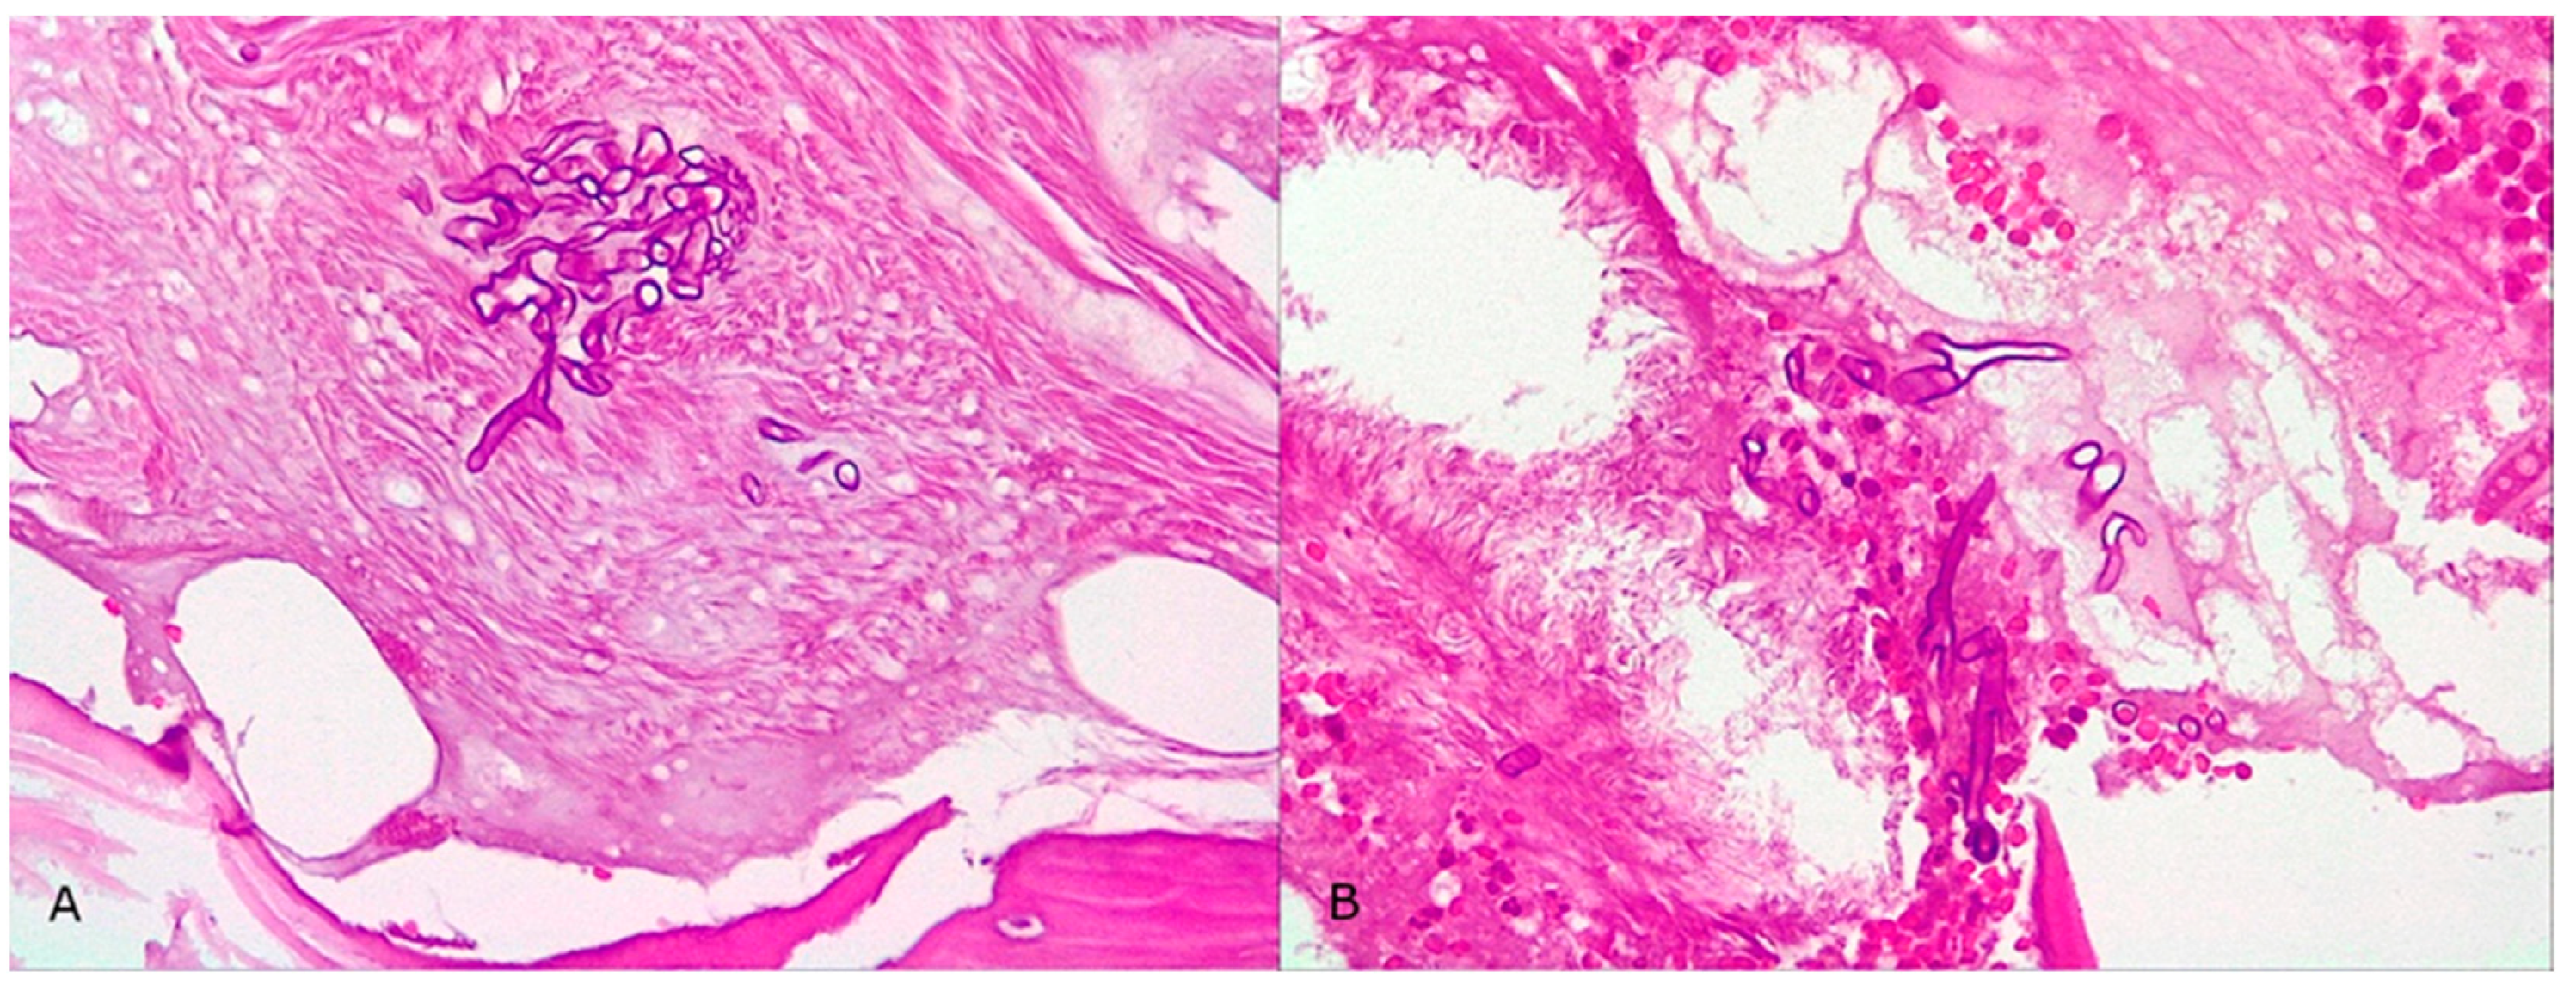

Subsequently, on 30 August 2022, he developed edema in the upper and lower eyelids, diffuse facial edema with Celsian signs, and associated centrofacial vascular necrosis at the level of the nasal pyramid with right orbital extension and the involvement of the right maxillary sinus, accompanied by headache, leading to admission to the Ear Nose Throat (ENT) department, Figure 2. A macroscopic anatomopathological examination revealed multiple necrotic fragments and a microscopic examination showed multiple histological sections represented by necrotic-inflammatory material, with numerous bacterial colonies and fungal filaments, and some branching at a 90-degree angle, consistent with mucormycosis, Figure 3. Cranial CT showed massive destructive infectious processes involving the maxillary sinuses, posterior ethmoid cells, and orbits with involvement of the right eye globes, possibly of mixed fungal and bacterial etiology, Figure 4. Surgical treatment was instituted by performing a total necrectomy of the centrofacial necrotic focus along with antibiotics (amoxicillin-sulbactam, cefoperazone) for 10 days and antifungal therapy with posaconazole (for 9 weeks) due to myelosuppression. Amphotericin B and isavuconazole were not available at that time in the hospital. Postoperative recovery was satisfactory, and subsequently, he was transferred to the hematology service for further specialized treatment.

Figure 3. Microscopic examination of the biopsy specimen (400× magnification). (A,B) Multiple histological sections represented by necrotic-inflammatory material, with numerous bacterial colonies and fungal filaments, some branching at a 90-degree angle, consistent with mucormycosis.